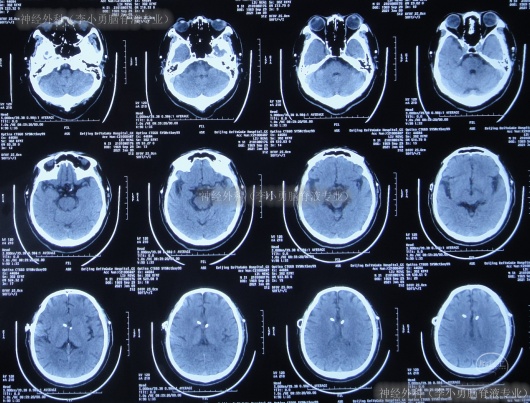

入院治疗10天即2021年1月18日(脑室外引流术后7天),查头颅CT示未见明显异常(图-15)。

图-15:2021年1月18日头颅CT